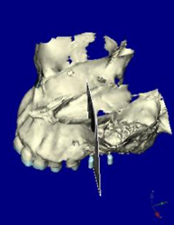

CTデータより3D画像を構築

左上に2本のインプラントを計画

上顎咬合面観

インプラントをシミュレーション